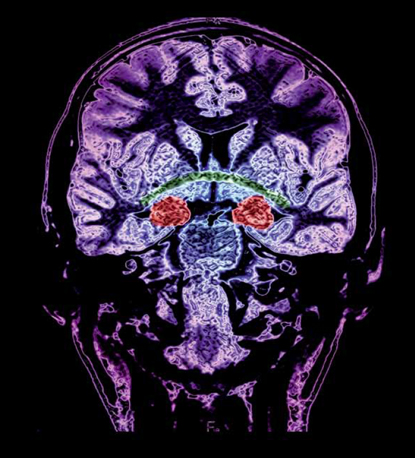

Les circuits de la peur

La crainte emprunte de nombreuses voies neuronales dans le cerveau. L’amygdale représente un centre essentiel dans ce réseau. Elle est d’ailleurs capable de générer une réponse physiologique à un danger avant même que celui-ci ne soit perçu consciemment

La peur se fraye plusieurs chemins dans le cerveau, mais tous passent par l’amygdale. L’activité de cette petite région située dans une partie interne du cerveau (au sein des régions limbiques du lobe temporal) est en effet étroitement liée au sentiment de crainte, notamment par le fait qu’elle est le siège de la mémoire émotionnelle. L’amygdale ne renferme pas une plus grande densité de neurones que les autres régions cérébrales. Mais elle a la particularité d’être celle qui possède le plus de connexions avec le reste du cerveau. En d’autres termes, elle peut recevoir beaucoup d’informations rapidement ou agir sur un nombre particulièrement grand de zones du système nerveux central.

«A l’heure actuelle, les neuroscientifiques connaissent bien les circuits de la peur dans le cerveau, explique Patrik Vuilleumier, professeur au Département des neurosciences fondamentales de la Faculté de médecine. Nous savons quelles aires sont mobilisées, nous connaissons l’enchaînement des réactions, les changements moléculaires qui interviennent, etc. L’amygdale représente une sorte de nœud central dans le circuit neuronal de la peur. C’est là en effet qu’est établie et gardée en mémoire l’association entre un stimulus extérieur et sa connotation positive ou négative.»